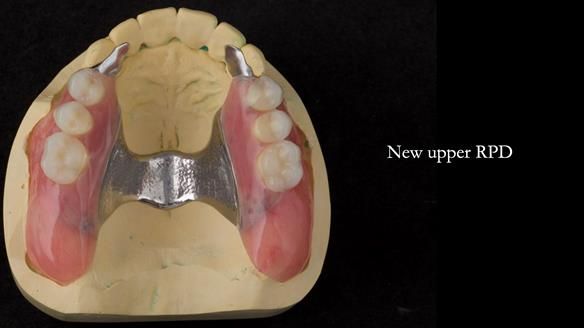

Replacement lower overdenture & upper RPD for Jackie

This Newsletter show Jackie’s case from start to finish – a technically demanding case involving replacing a telescopic crown-supported lower overdenture and an upper precision attachment-retained partial denture.

With the benefit of hindsight, I still dislike the upper 6 crowns – changing them would have dramatically improved the smile. But Jackie was content with how they looked and understandably didn’t want to open a can of worms.